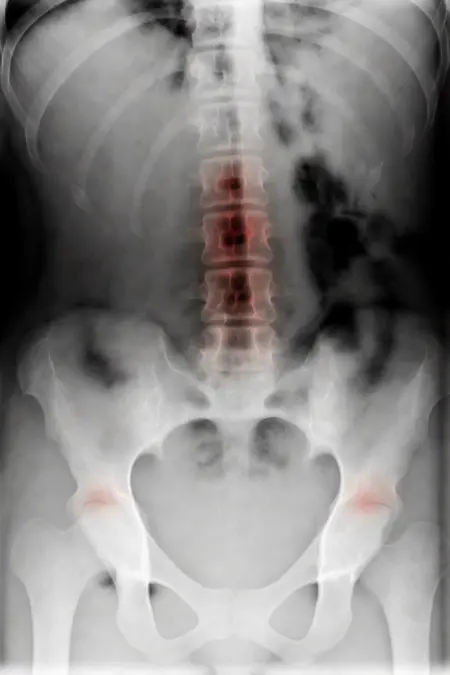

アートや写真の編集用に設計されたFlux Kontextのようなモデルを、医療画像、たとえば「単純な」骨折の赤色マーキングに使用できるか?

即答:面白い結果を出すが、過剰に反応し、医療ツールとしては信頼性に欠ける。これはアイデアを試すためのプロトタイプに過ぎない。

さらに攻撃的な設定(例:rk beta57、Denoise 1.0)では、**偽陽性100%、検出100%**という馬鹿げた結果に:すべてを赤で塗りつぶし、健常部もほぼすべて骨折と誤認する。未経験の目には区別がつかない。

Civitai用に作成した、100% AI生成の合成ミニデータセット(健康なX線10枚、骨折のあるX線10枚)でテスト:

- 健康な骨での偽陽性:100%

- 骨折検出:≈ 45%

重要

このLoRaは視覚的実験用のみです。

医療機器ではありません。信頼性がなく、臨床診断には使用しないでください。

もちろん、このツールはオープンソースで、高速(1回の分析に25秒)、一般のデスクトップPCで動作するため、今後このコンセプトをさらに実験する価値はあると思います…今後の展開に注目です!